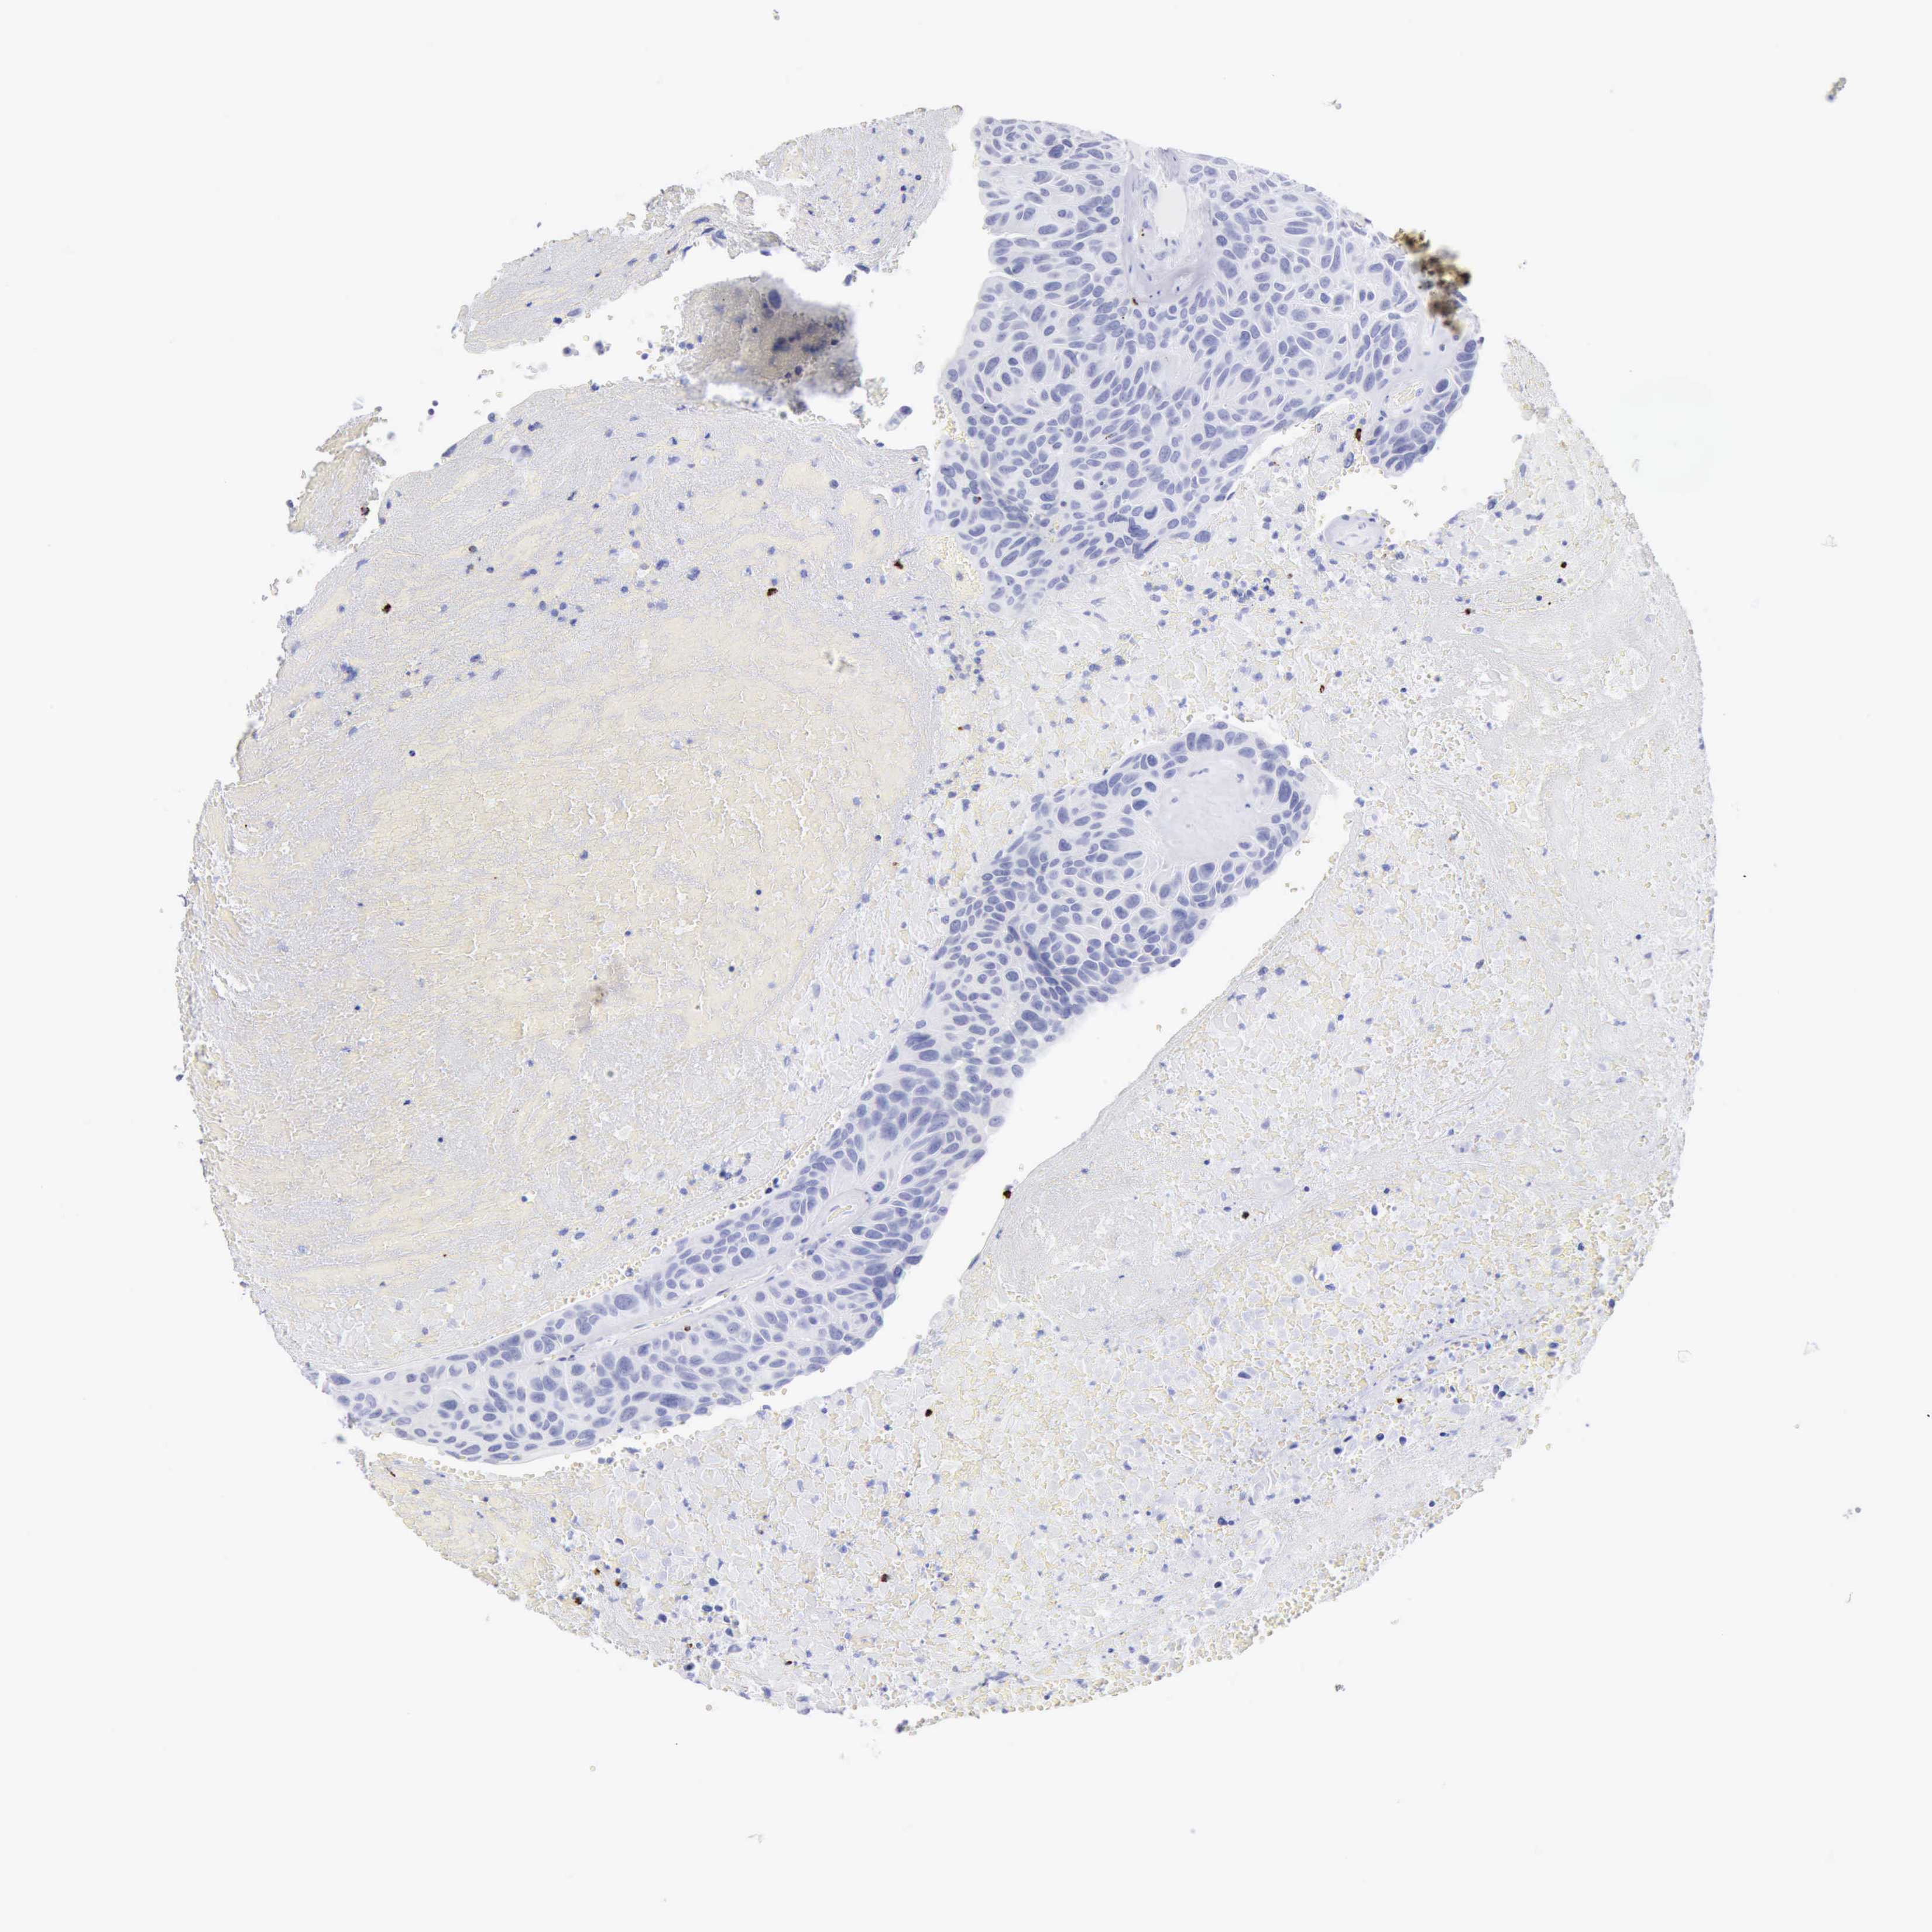

UROTHELIAL CANCER - Protein expressioni

A mouse-over function shows sample information and annotation data. Click on an image to view it in a full screen mode. Samples can be filtered based on level of antibody staining by selecting one or several of the following categories: high, medium, low and not detected. The assay and annotation is described here.

Antibody stainingi

Antibody staining in the annotated cell types in the current human tissue is reported as not detected, low, medium, or high, based on conventional immunohistochemistry profiling in selected tissues. This score is based on the combination of the staining intensity and fraction of stained cells.

Each image is clickable and will lead to virtual microscopy that enables deeper exploration of all samples and also displays staining intensity scores, fraction scores and subcellular localization as well as patient and tissue information for each sample.

Antibody HPA003418

Antibody CAB000376

Urothelial carcinoma, High grade

Urothelial carcinoma, Low grade